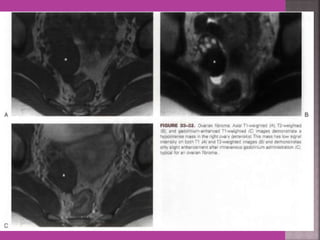

3. ovarian cancer—malignant versus

benign mass, ascites , retroperitoneal node >

1cm , Bowel bladder , ano rectal . Parietal

peritoneum , liver and or omental

metastasis.

 Gynaecological cancers--- 1. Cervical cancer –extent of parametrium and pelvic organs , pelvic L.N., Endocervical. 2.Endometrial cancer –Myometrial invasion, downward extension to cervix. 3. ovarian cancer—malignant versus benign mass, ascites , retroperitoneal node > 1cm , Bowel bladder , ano rectal . Parietal peritoneum , liver and or omental metastasis. 4. Pregnancy --- complicated by genital cancers